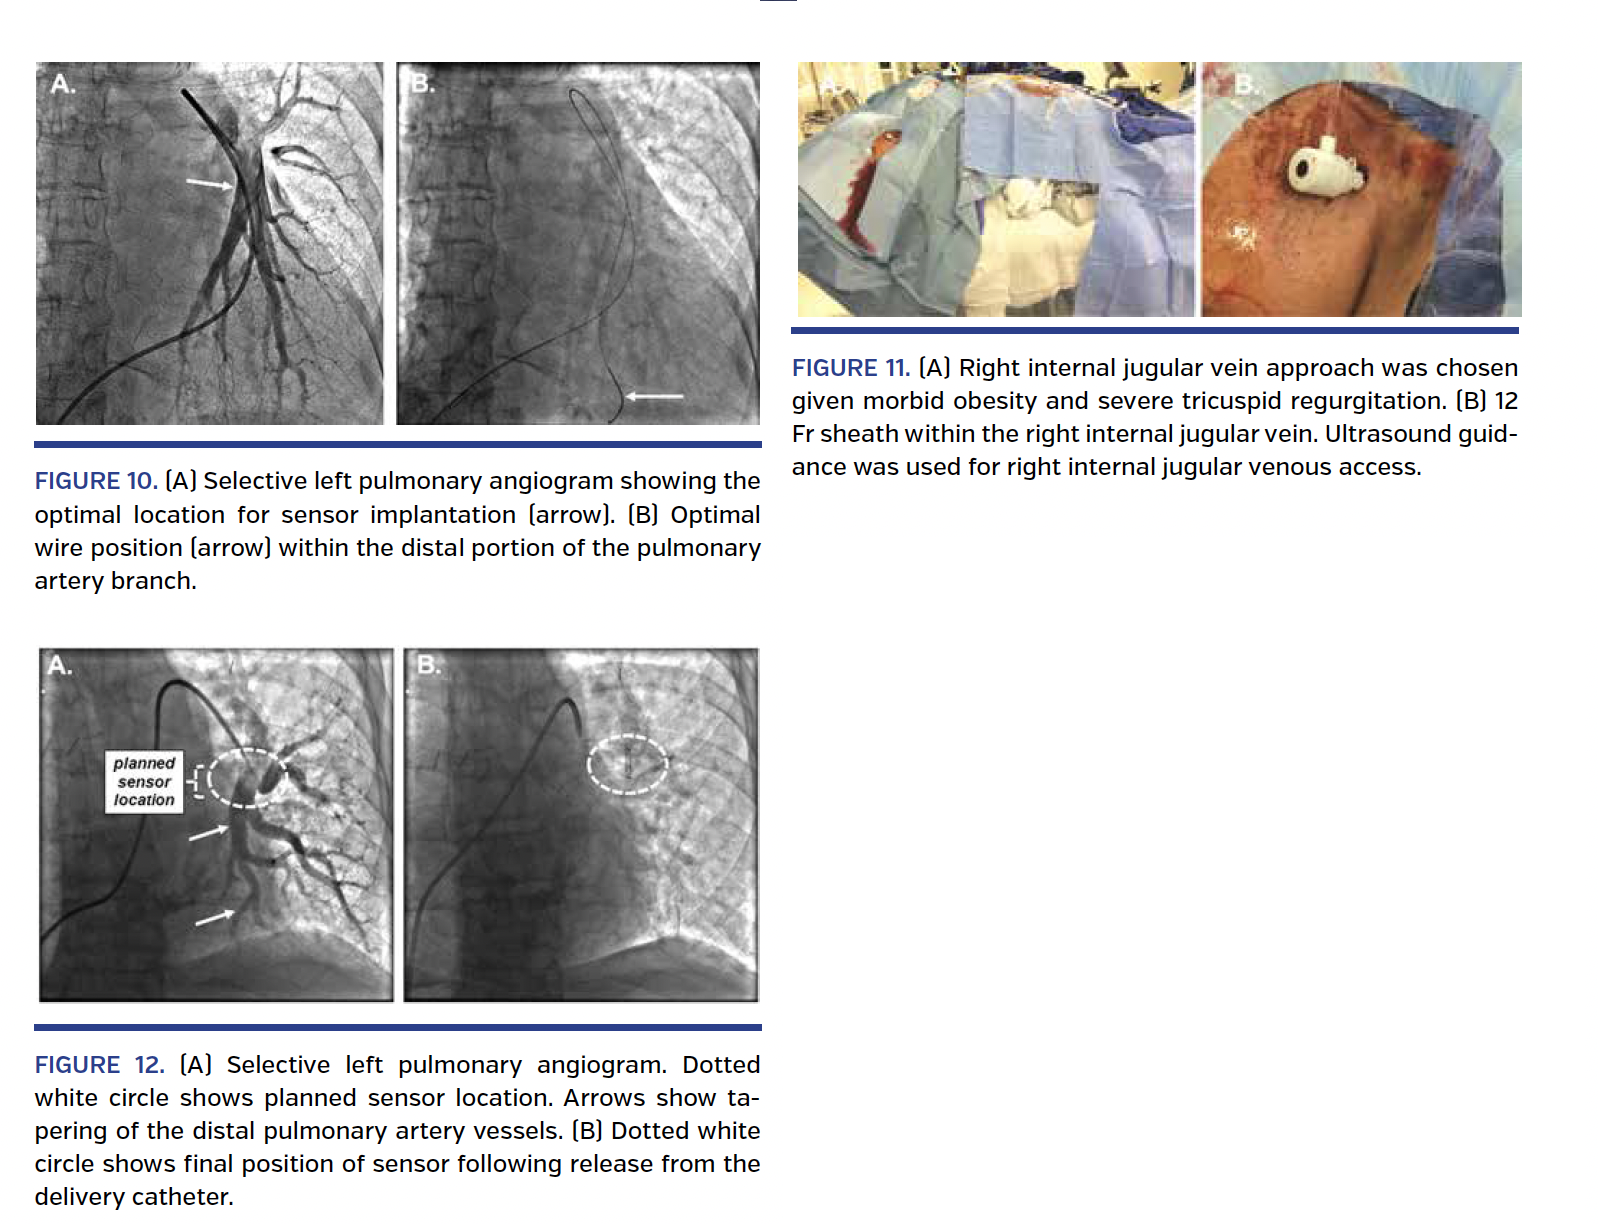

Case #1. Straightforward implantation. A 65-year-old female with CHF with preserved ejection (HFpEF), prior aortic valve replacement, severe left ventricular hypertrophy, and three prior episodes of HF requiring hospitalization over the last year was referred for CardioMEMS implantation. Procedural imaging showed a left-sided pulmonary artery branch measuring approximately 10 mm in diameter (Figure 10). A 0.018˝ wire was placed into a distal branch and provided excellent support. The sensor was implanted without difficulty.

Case #2. Severe tricuspid regurgitation. A 52-year-old male with morbid obesity (body mass index, 36 kg/m2; chest circumference, 64 inches) and HF with reduced ejection fraction (HFrEF), ventricular tachycardia, and three prior episodes of HF requiring hospitalization over the last year was referred for CardioMEMS implantation. A recent transthoracic echocardiogram showed an ejection fraction of <25%, severe tricuspid regurgitation, and moderate pulmonary hypertension. Given the presence of severe tricuspid regurgitation and morbid obesity, venous access was obtained using ultrasound guidance of the right internal jugular vein (Figure 11). A selective pulmonary angiogram showed a left-side pulmonary artery branch measuring approximately 10 mm in diameter. Sensor advancement across the tricuspid valve was straightforward and the sensor was implanted without difficulty.

Case #4. Non-optimal vessel location for sensor location. A 68-year-old male with coronary artery disease, prior myocardial infarction, prior coronary artery bypass surgery, and multiple prior coronary stent procedures with HFrEF and three prior episodes of HF requiring hospitalization over the last year was referred for CardioMEMS implantation. A 7 Fr balloon wedge catheter was advanced from the right common femoral vein to the left pulmonary artery and a selective pulmonary angiogram was obtained. Significant tapering of the distal pulmonary artery branch vessels was noted (Figure 12). The optimal sensor location was thought to be slightly distal, to allow apposition of the nitinol loops to the vessel wall and to avoid having the sensor “float” in the proximal portion of the branch. A 0.018˝ CardioMEMS guidewire was placed into the distal portion of the pulmonary artery branch and the sensor was released without difficulty. There was no movement of the sensor post deployment.